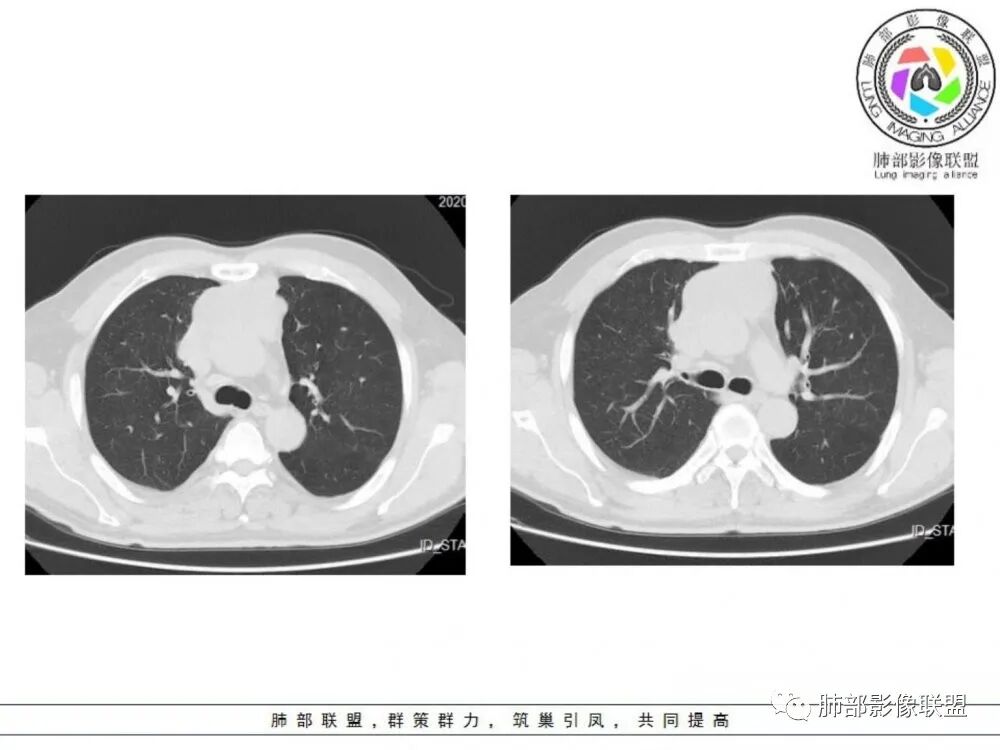

男性患者,65岁,前胸后背疼痛一个月。影像学前上纵隔分叶状的软组织肿块,肿块形态怪异,偏软,位于大血管间隙前,并有向血管后间隙发展的趋势,平扫CT值为40左右,增强扫描中心部未见强化,周围轻度的强化,约为50左右。前上纵隔的疾病谱包抬胸廓内甲状腺肿、胸腺瘤/癌、畸胎瘤、淋巴瘤。少见的心包囊肿或支气管囊肿。根据肿块的形态及强化特点,首先还是排除了胸内甲状腺肿及胸腺来源的肿物,这类的肿物强化比较明显。畸胎瘤成分比较复杂,具有软组织钙化或者脂肪类的组织,这个肿物虽然在平扫的时候好像有斑点状的钙化灶,但是总体成分还是比较单一,所以还是排除畸胎瘤的诊断。所以这样的情况是考虑:淋巴类的肿瘤,注意排除心包的囊肿或支气管来源的囊肿。

老年男性患者,前膈软组织肿块,边缘轮廓不光整,边界似乎尚清晰,内见小点状钙化灶,平扫密度欠均匀,增强后轻度强化表现,边缘有些斑片状的高强化区。综合考虑胸腺瘤或胸腺鳞癌,神经内分泌癌强化弱了一些。患者年龄较大,生殖细胞肿瘤不考虑,淋巴瘤血管包绕不够,可能性不大

老年男性,前胸后背痛一个月,前纵隔不规则肿块,分叶,向纵隔血管间隙进入,且与纵隔血管分界不清,增强边缘轻度强化,中间可见无强化区,似见点状钙化,PET为高代谢,考虑为来源于胸腺,胸腺瘤或胸腺鳞癌可能

中老年男性,前纵隔占位,基本居中,向两侧生长;边缘膨隆分叶,部分边界不清,增强不均匀轻中度强化,坏死区边界不清;周围多发增大淋巴结,考虑恶性。主要在胸腺癌、胸腺瘤、淋巴瘤之间鉴别。病灶偏软,有钻缝样生长,这些征象偏向于淋巴瘤。但此例老年患者,病灶内有点状钙化,缺乏结节堆砌感,倾向胸腺癌诊断。